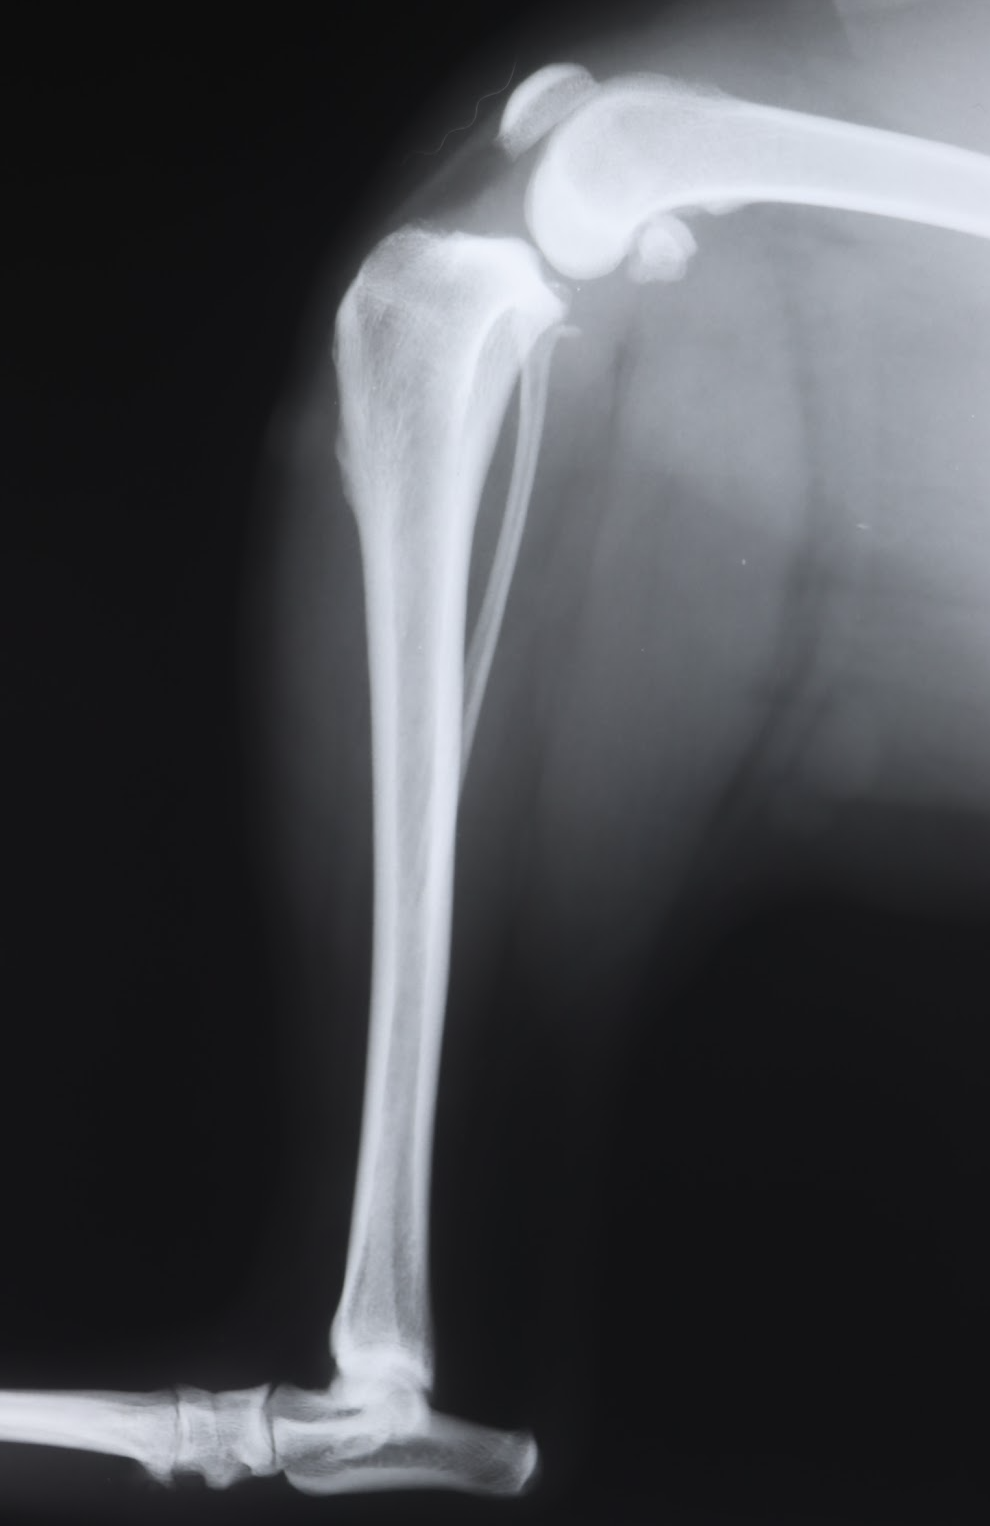

犬の前十字靭帯断裂の手術には、主にTPLOとLSSという2つの方法があります。TPLOは、脛骨の高平部を切断し、角度を変えることで膝関節の安定性を高める手術です。一方、LSSは、膝の外側に糸を通し、関節の安定性を図る手術です。

一般的に、TPLOは大型犬や活動的な犬に適しており、長期的な安定性が期待できます。一方、LSSは小型犬や中等度の症例に適していますが、大型犬や高活動量の犬では、糸が切れるリスクや再断裂のリスクが高まる可能性があります。

今回、当院で手術したのは、35kgのピットブルという大型犬で、体重も重く、活動量も高いということもあり、LSSは通常、適応外の手術となります。しかも肥満犬です。本来は高度医療施設でのTPLOをするのが最良です。(当院でTPLOを行っておらず、LSSは対応しています)

LSSは、膝関節の安定性を糸で保つため、強い力がかかると糸が切れてしまい、手術の効果が得られない可能性があります。特に、ピットブルのような筋肉質な犬種は、関節にかかる負荷が大きい傾向があり、LSSの成功率がさらに低くなる可能性があります。

通常、LSS手術後にはギプス固定は行いませんが、今回の症例では、手術の成功率を高めるために、術後にギプス固定を行うという、やや特殊な方法を選択しました。これは、LSSが大型犬に適さないというリスクを補うため、術後の関節の安定性を高めることを目的としたものです。また、ピットブルのような筋肉質な犬種は、術後の関節の動きが大きくなりやすく、ギプス固定によって過度の動きを抑制することで、関節への負担を軽減する効果も期待できます。

LSSの治癒原理は、膝関節の脇に糸をかけ、ももとすねの骨の位置を適した位置で安定化させ、その後自然に起こる関節内や縫合糸の周囲の線維化を利用し、継続的な安定化を得るというものです。糸はしばらくするとゆるむので、恒久的な靭帯の代わりにはなりません。どんな手術方法でも切れた靭帯はつなげることはできません。線維化で安定化させるには、しばらくの間ギプス固定が有効であると考えます。よって、治癒原理を考えれば、一般的な小型犬においても、LSSのあとにはギプス固定は適しているかもしれません。

手術は無事に終了し、一ヶ月ほどギプス固定を行った結果、順調に回復しました。